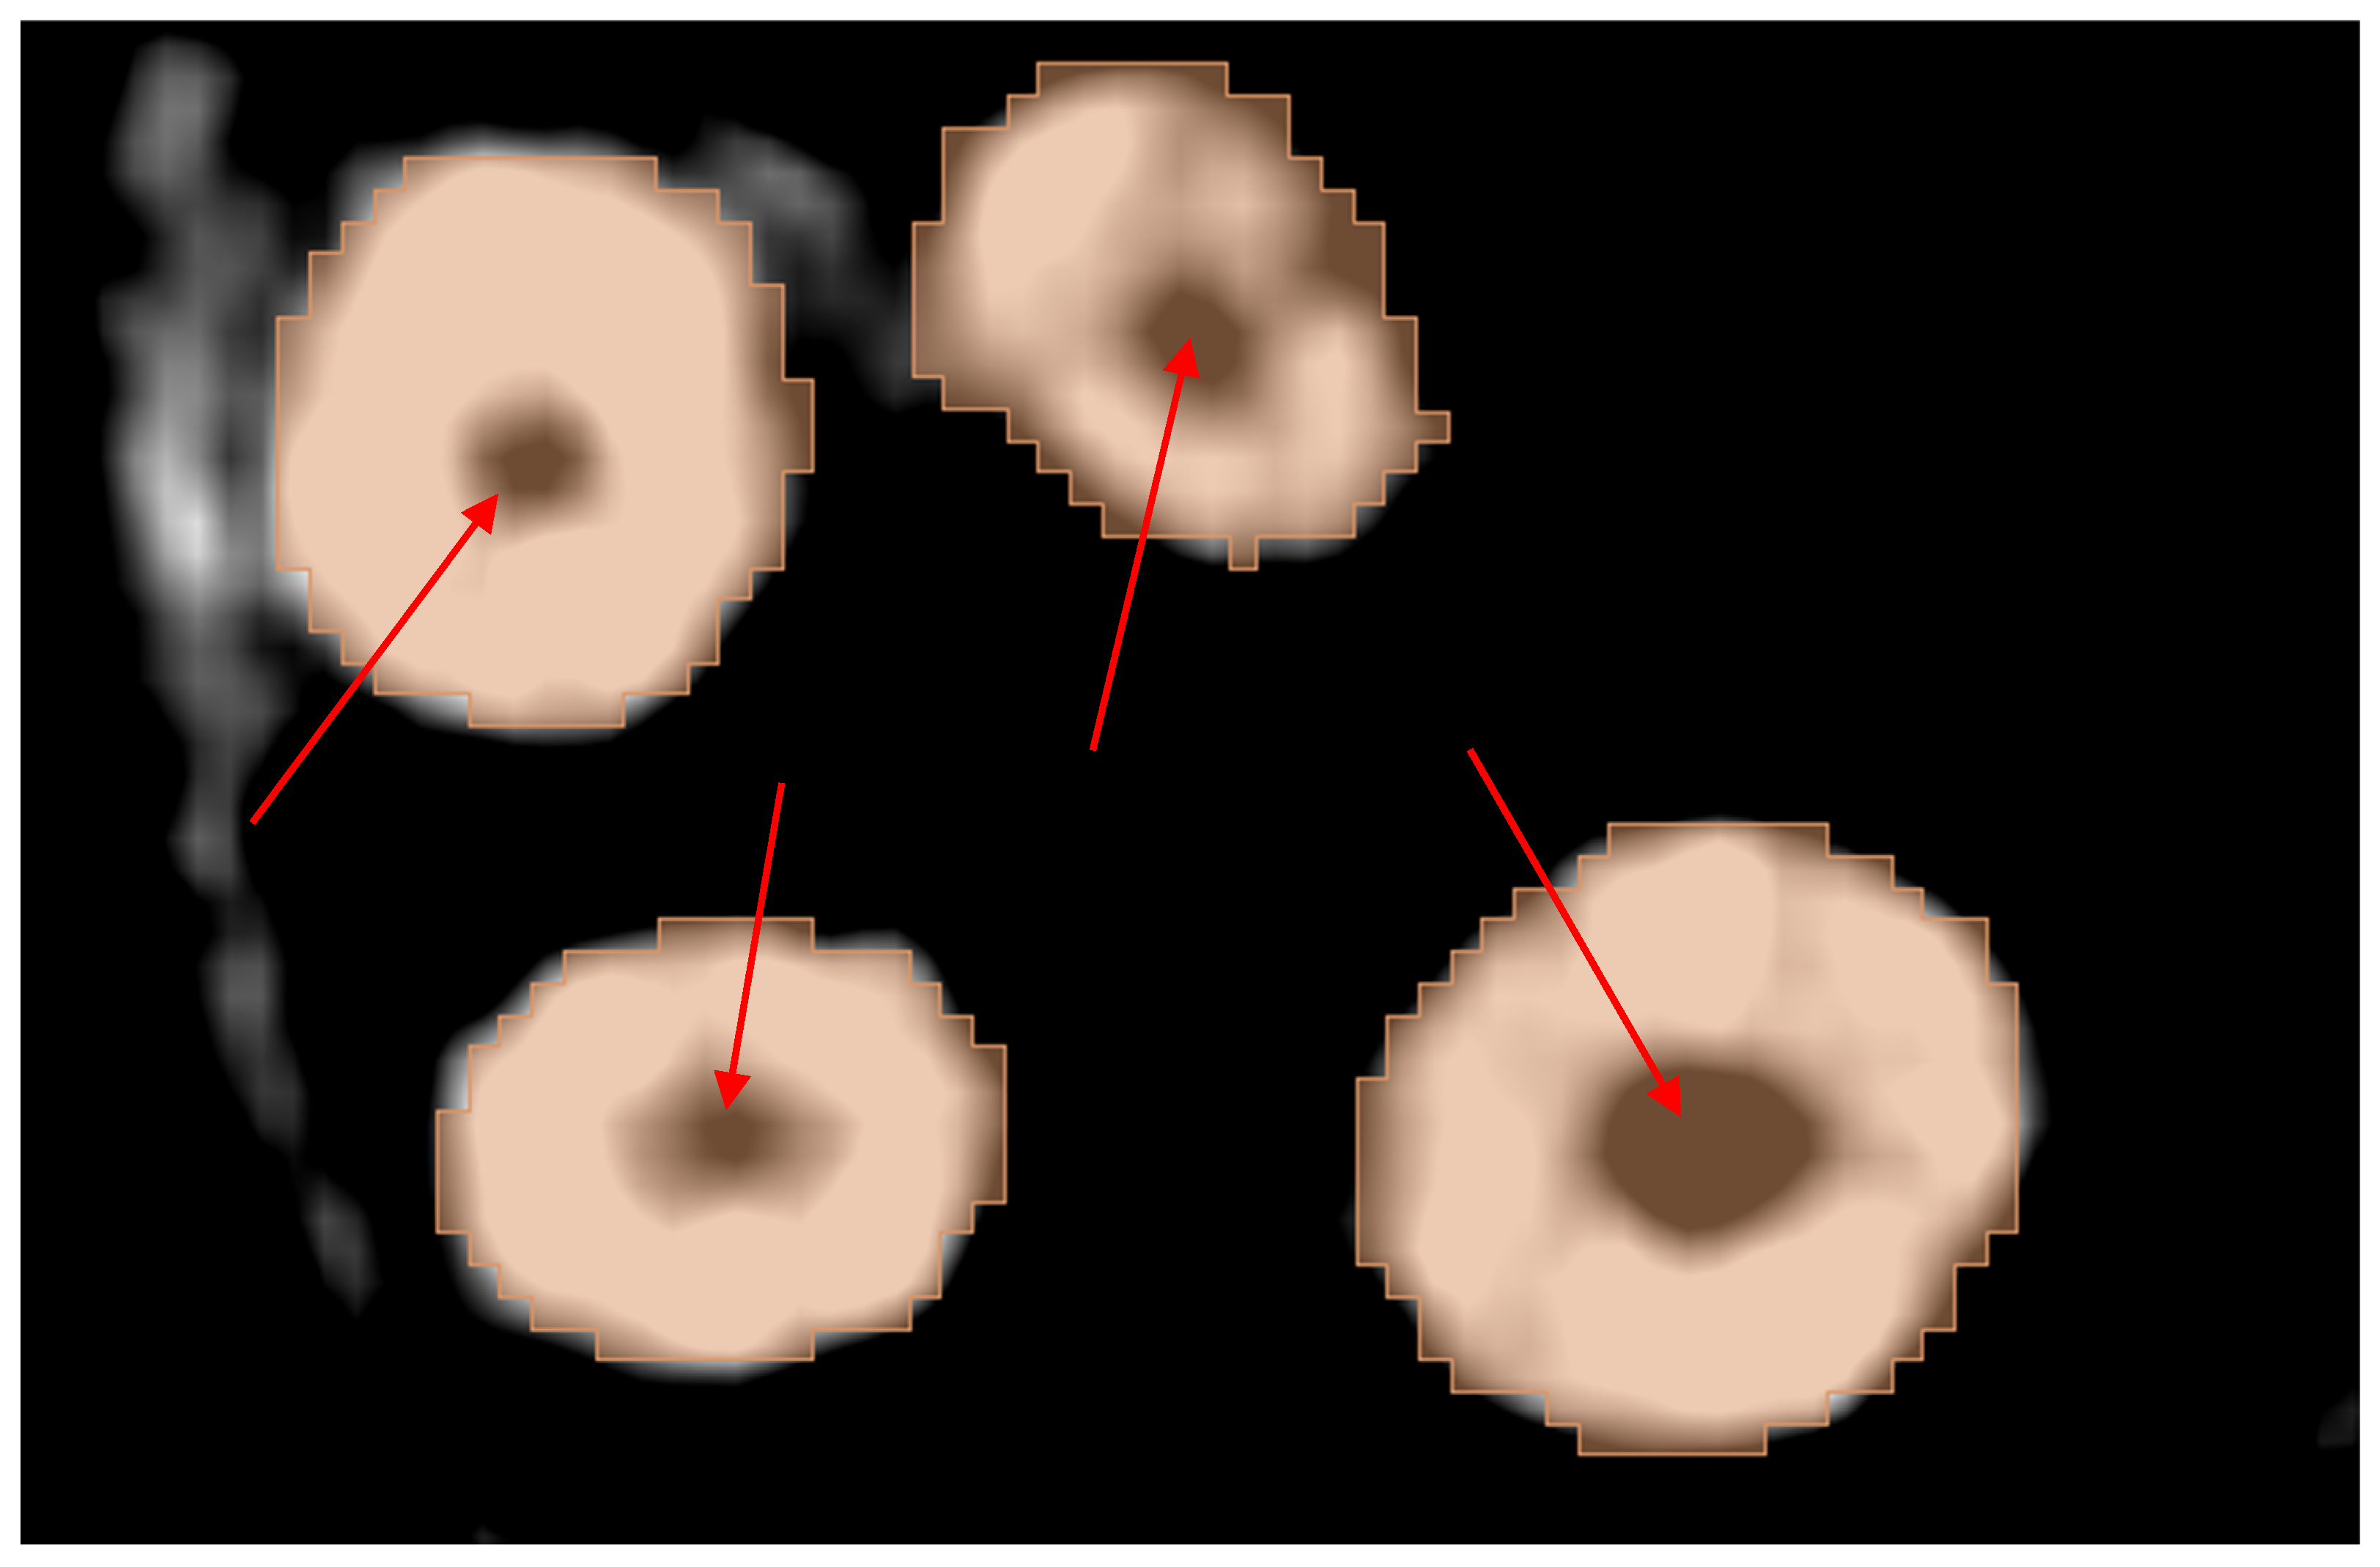

2.3.3. Thresholding Masking